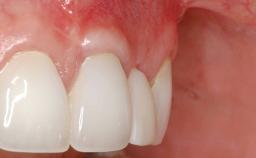

A 30-year-old woman was referred by her general dentist for evaluation of an esthetic complication related to previous implant treatment for congenitally missing maxillary lateral incisors. The patient’s chief complaint was the inadequate esthetic appearance of her smile. The case demonstrates the use of a combined approach to achieve optimal results. Two different flap designs - a tunnel technique and a coronally advanced flap - are employed based on the surgical objectives for the affected site.

Periodontal Plastic Surgery and Prosthetic Procedures to Treat Peri-Implant Soft-Tissue Dehiscences

Soft Tissue Grafting Yes